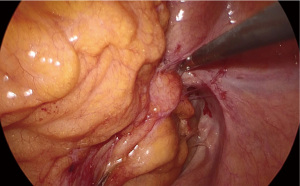

The patient was positioned supine on the operative table with the legs abducted. Under general anesthesia, a cystoscopy was performed, and a 6 Fr Pollack catheter was introduced in the left ureter to allow intraoperative injection of ICG. Pneumoperitoneum was induced through a Veress needle placed in the umbilicus. Four ports (two 12-mm and two 5-mm) were placed as for laparoscopic left colectomy (Figure 6). Upon exploration of the abdominal cavity, the sigmoid was tenaciously adherent to the posterior-lateral aspect of the bladder (Figure 7). The small bowel was retracted away from the operative field. Partial mobilization of the descending and sigmoid colon was performed using the monopolar hook and harmonic scalpel. The inferior mesenteric artery and vein were clipped with Hem-o-lok and sectioned (Figure 8). The left ureter was visually identified and followed along its route toward the pelvis, then it could not be clearly distinguished from the pseudotumor involving the sigmoid colon and the bladder. Infusion of 5 mL of ICG through the ureteral catheter allowed to visualize the left ureter (Figure 9) and guided the dissection of the sigmoid from the bladder wall. At the end of dissection, the bladder wall appeared undamaged, and a methylene blue test was performed to exclude urinary leakage (Figure 10). A 5-cm laparotomy in the right iliac fossa was performed and the Alexis® wound retractor was placed. A curved linear stapler (Contour®) was introduced and sealed with a surgical glove to maintain the pneumoperitoneum. After rectal stapling, a 5 mL intravenous bolus of ICG was injected to test for colonic perfusion and to identify the ideal site for the anastomosis on the descending colon. A standard transanal Knight-Griffen colorectal anastomosis was performed using a 29-mm circular stapler. Two abdominal drains were left in the pelvis, and the abdominal incisions were closed. Total duration of the procedure was 220 minutes, and blood loss was <100 mL. Video 1 shows the whole surgical procedure.